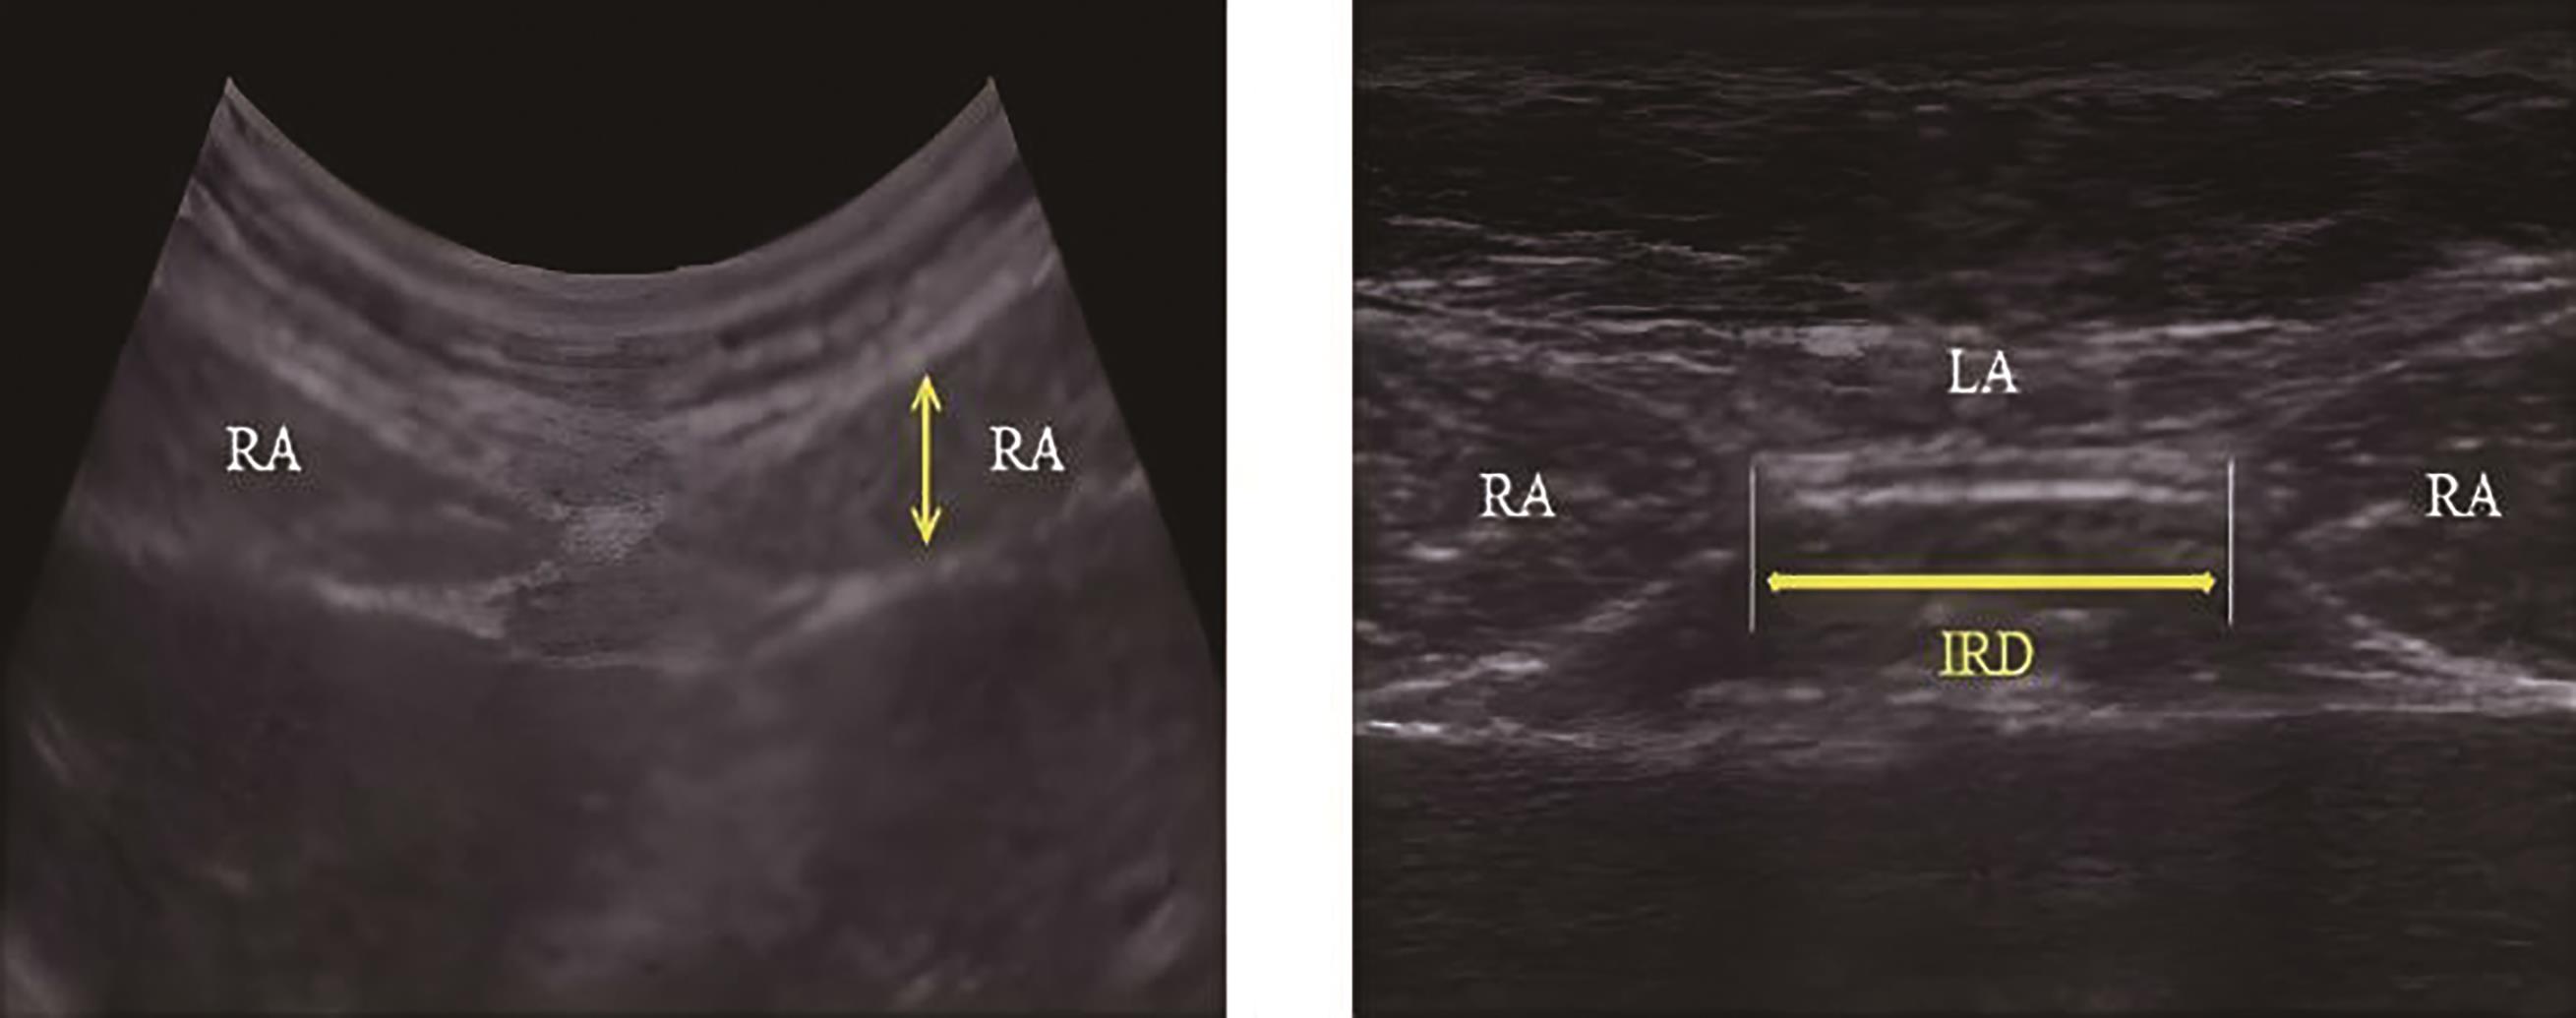

• 高频超声用于评估Flexi-bar运动训练联合脉管电刺激治疗后产后腹直肌分离变化的临床价值

摘要:目的 探讨高频超声用于评估Flexi-bar运动训练联合脉管电刺激治疗后产后腹直肌分离变化的临床价值。方法 回顾性分析常州市妇幼保健院2022年5月—2024年4月收治的87例产后腹直肌分离患者的病历资料。根据治疗方法不同将患者分成观察组(45例)与对照组(42例),观察组采用Flexi-bar运动训练联合脉管电刺激治疗,对照组采用脉管电刺激治疗。采用高频超声评估患者腹直肌间距离,对比两组的腹围、腹直肌间距离、腹直肌均方根、肌纤维力及生活质量。结果 观察组治疗前后下腹围、中腹围和上腹围的差值均大于对照组(P <0.05)。观察组治疗前后屈曲状态下脐下3 cm、脐上3 cm和脐中腹直肌间距离的差值均大于对照组(P <0.05)。观察组治疗前后静息状态下脐下3 cm、脐上3 cm和脐中腹直肌间距离的差值均大于对照组(P <0.05)。观察组治疗前后腹直肌最大自主等长收缩振幅均方根、盆底Ⅱ类肌纤维肌力平均值、盆底Ⅰ类肌纤维肌力最大值的差值均大于对照组(P <0.05)。观察组治疗前后生活质量评分的差值大于对照组(P <0.05)。结论 Flexi-bar运动训练联合脉管电刺激可改善产后腹直肌分离患者生活质量与盆底肌纤维肌力,缩小患者腹围,促进产后腹直肌分离的恢复,且高频超声可有效评估患者恢复情况与腹直肌分离情况。